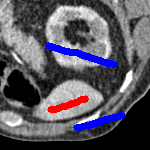

3 Alternative Selective Segmentation Models

We now introduce two recent methods that incorporate user input to perform selective segmentation. Each involves input in the form of foreground/background regions to indicate relevant structures of interest. An example of this can be seen in Fig. 18, where red regions indicate foreground and blue regions indicate background. We compare against the work of Nguyen et al. Nguyen:12 , which uses a similar convex relaxation framework to the proposed approach, and Dong et al. SRW , which uses a variation of the random walk approach. We summarise the essential aspects of each approach in the following.